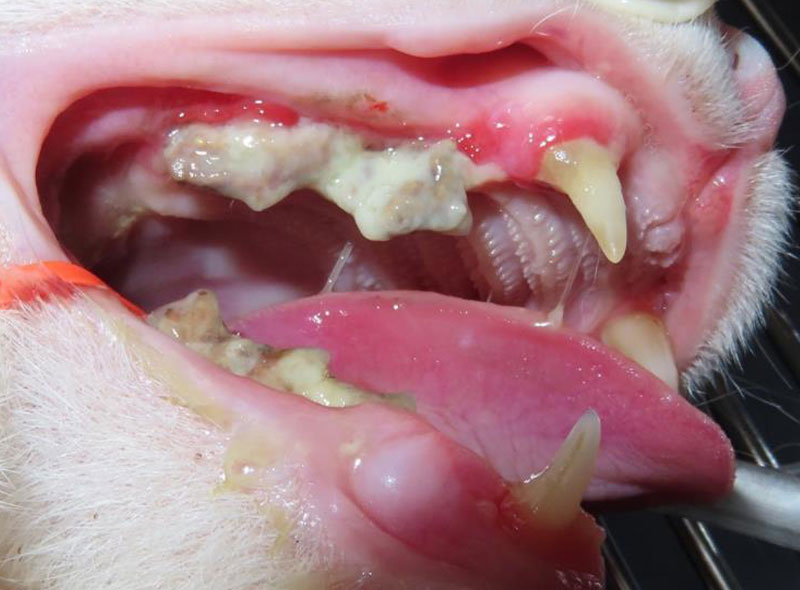

歯の吸収病巣

吸収性病巣

猫に多く見られ、かつては猫破歯細胞性吸収病巣と呼ばれていました。

最近は犬にも見られます。

その名の通り、破歯細胞という歯を壊し溶かしてしまう細胞が歯を吸収し、吸収された部位には肉芽が増殖するので、出血しやすく、痛みを伴います。タイプがいくつかありますが、進行するに従い、歯がなくなったように見えたり、逆に肉芽や出血、周囲の炎症を伴うため歯石が過剰に蓄積していることもあります。

1本の歯だけでなく、複数の歯に見られることも多く、歯石を除去して初めてわかることもあります。吸収病巣が歯髄まで進んだ歯は、噛むことで痛みを感じるため、犬や猫はこの歯を避けて噛むような仕草をします。また、とても痛いので、病巣になっている歯の歯磨きを嫌がることが多いです。

猫の吸収病巣

歯頸部の骨が虫食い状に溶けています。見た目は、一見歯周病の歯に見えますが、歯冠部のみが動揺し、根っこは残存したままとなります。この状態では、根っこの神経が露出したままとなり、痛みや炎症は治りません。